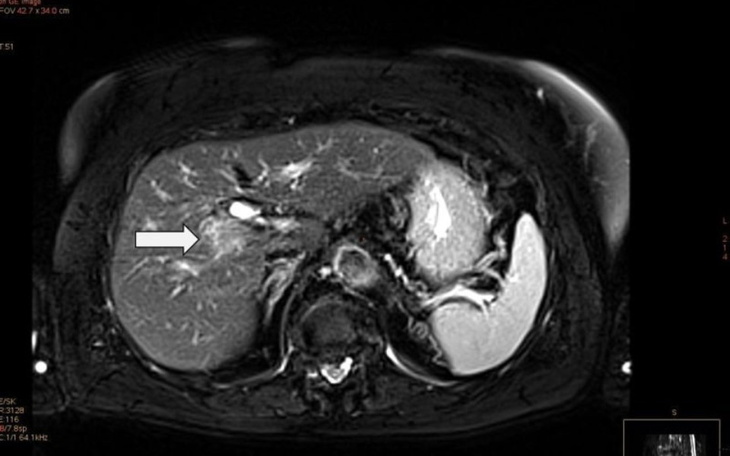

Cześć jestem Sanda córka Pani Eweliny moja mama ma guza na wontrobie jest konieczna operacja